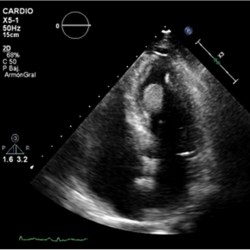

Figure 4.

3D-Zoom. Detailed view of the mass.

The patient had poor outcome and died, autopsy was not performed and therefore histologic study of the mass was not available. Although the PET study showed perfusion of the mass and contrast echocardiographic study demostrated perfusion. Based on the clinical scenario and the PET, 3D-transthoracic echocardiogram and contrast findings, the mass was suspected to be a cardiac metastasis. These images show sole intracardiac mass (probably metastasis) with no other cardiac involvement in a patient with metastatic lung cancer disease. This is an unusual case because of the atypic pattern of metastases in the heart [1], that more often is characterized by pericardial effusion and local extension [2] or involvement and atrial masses with invasion to the heart by the pulmonary veins [3]. Haematogenic dissemination is the most probable mechanism for this case. Three-dimensional echocardiography is useful in diagnosis and monitoring of myocardial masses [4, 5].